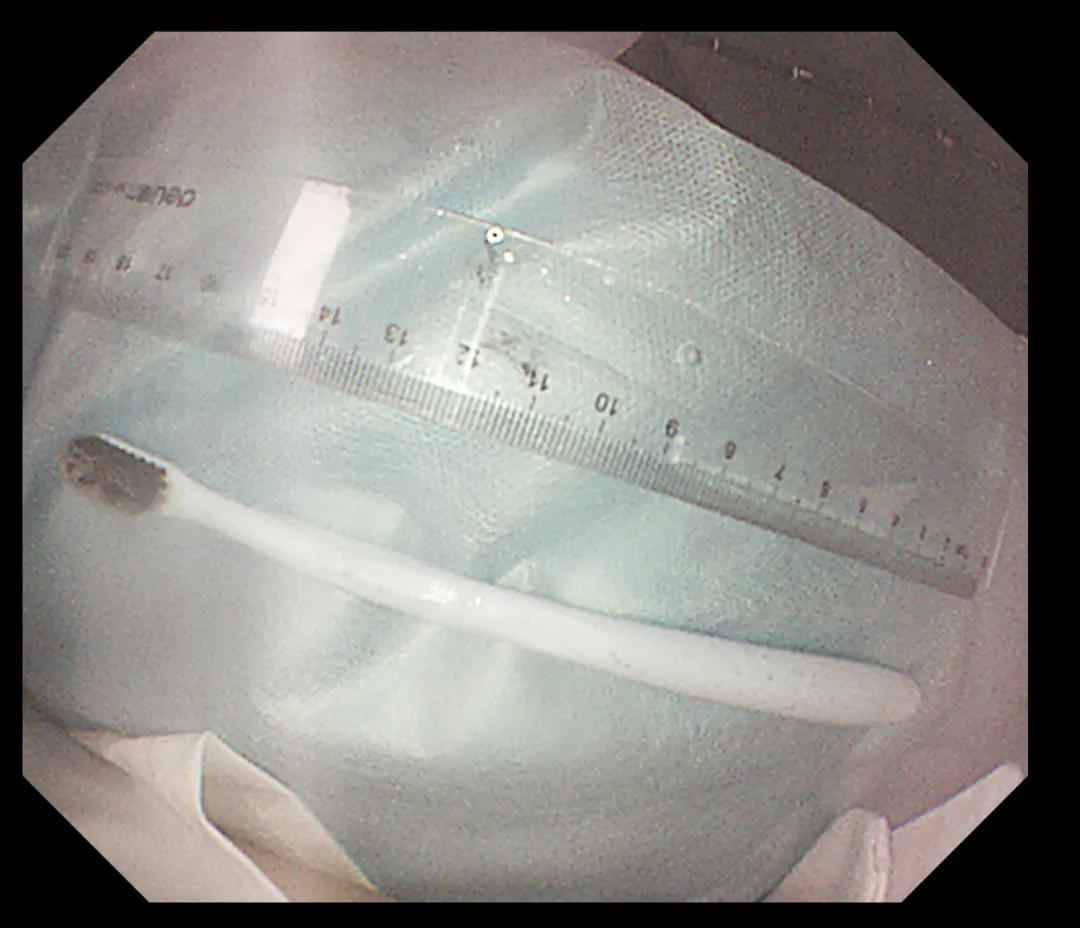

經(jīng)過反復(fù)努力嘗試,圈套器終于緊緊的套住異物,使牙刷長軸盡量與食道長軸平行,適當(dāng)注氣擴(kuò)張食道腔。經(jīng)過不懈努力,順利將其取出,取出牙刷經(jīng)測量長度約20cm,似乎這條細(xì)細(xì)的胃鏡就是一條連接希望的生命線。此時(shí)在場所有人懸著的那顆心也終于落下。術(shù)后小楊癥狀逐漸消失,生命指征平穩(wěn),情緒也平靜下來。